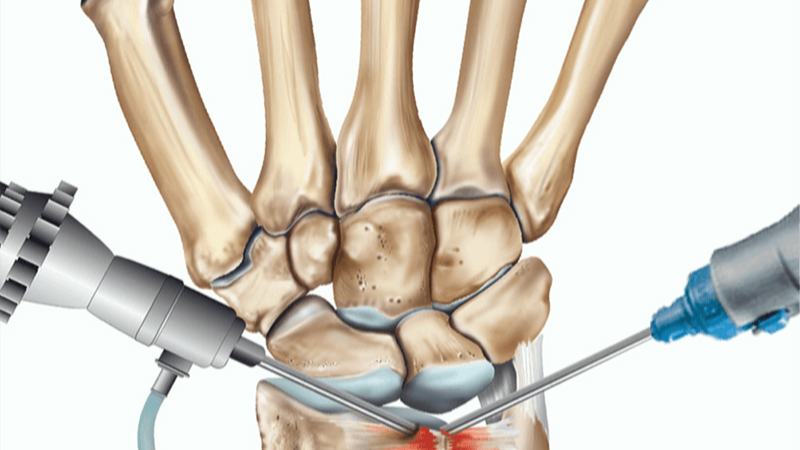

Siddarth Kamath K, Jayakrishnan KN, Acharya A, Bhat AK. 'Vanishing carpal bones' in a patient with congenital adrenal hyperplasia - A diagnostic dilemma. J Orthop. 2020;22:493-496.

www.researchgate.net/publication/344589487_Vanishing_carpal_bones'_in_a_patient_with_congenital_adrenal_hyperplasia_-_A_diagnostic_dilemma

Narayana Kurup JK, Shah HH. A rare case of rubber band syndrome of wrist with distal radius and ulna fracture. J Orthop. 2020;20:60-62.

pubmed.ncbi.nlm.nih.gov/32042231